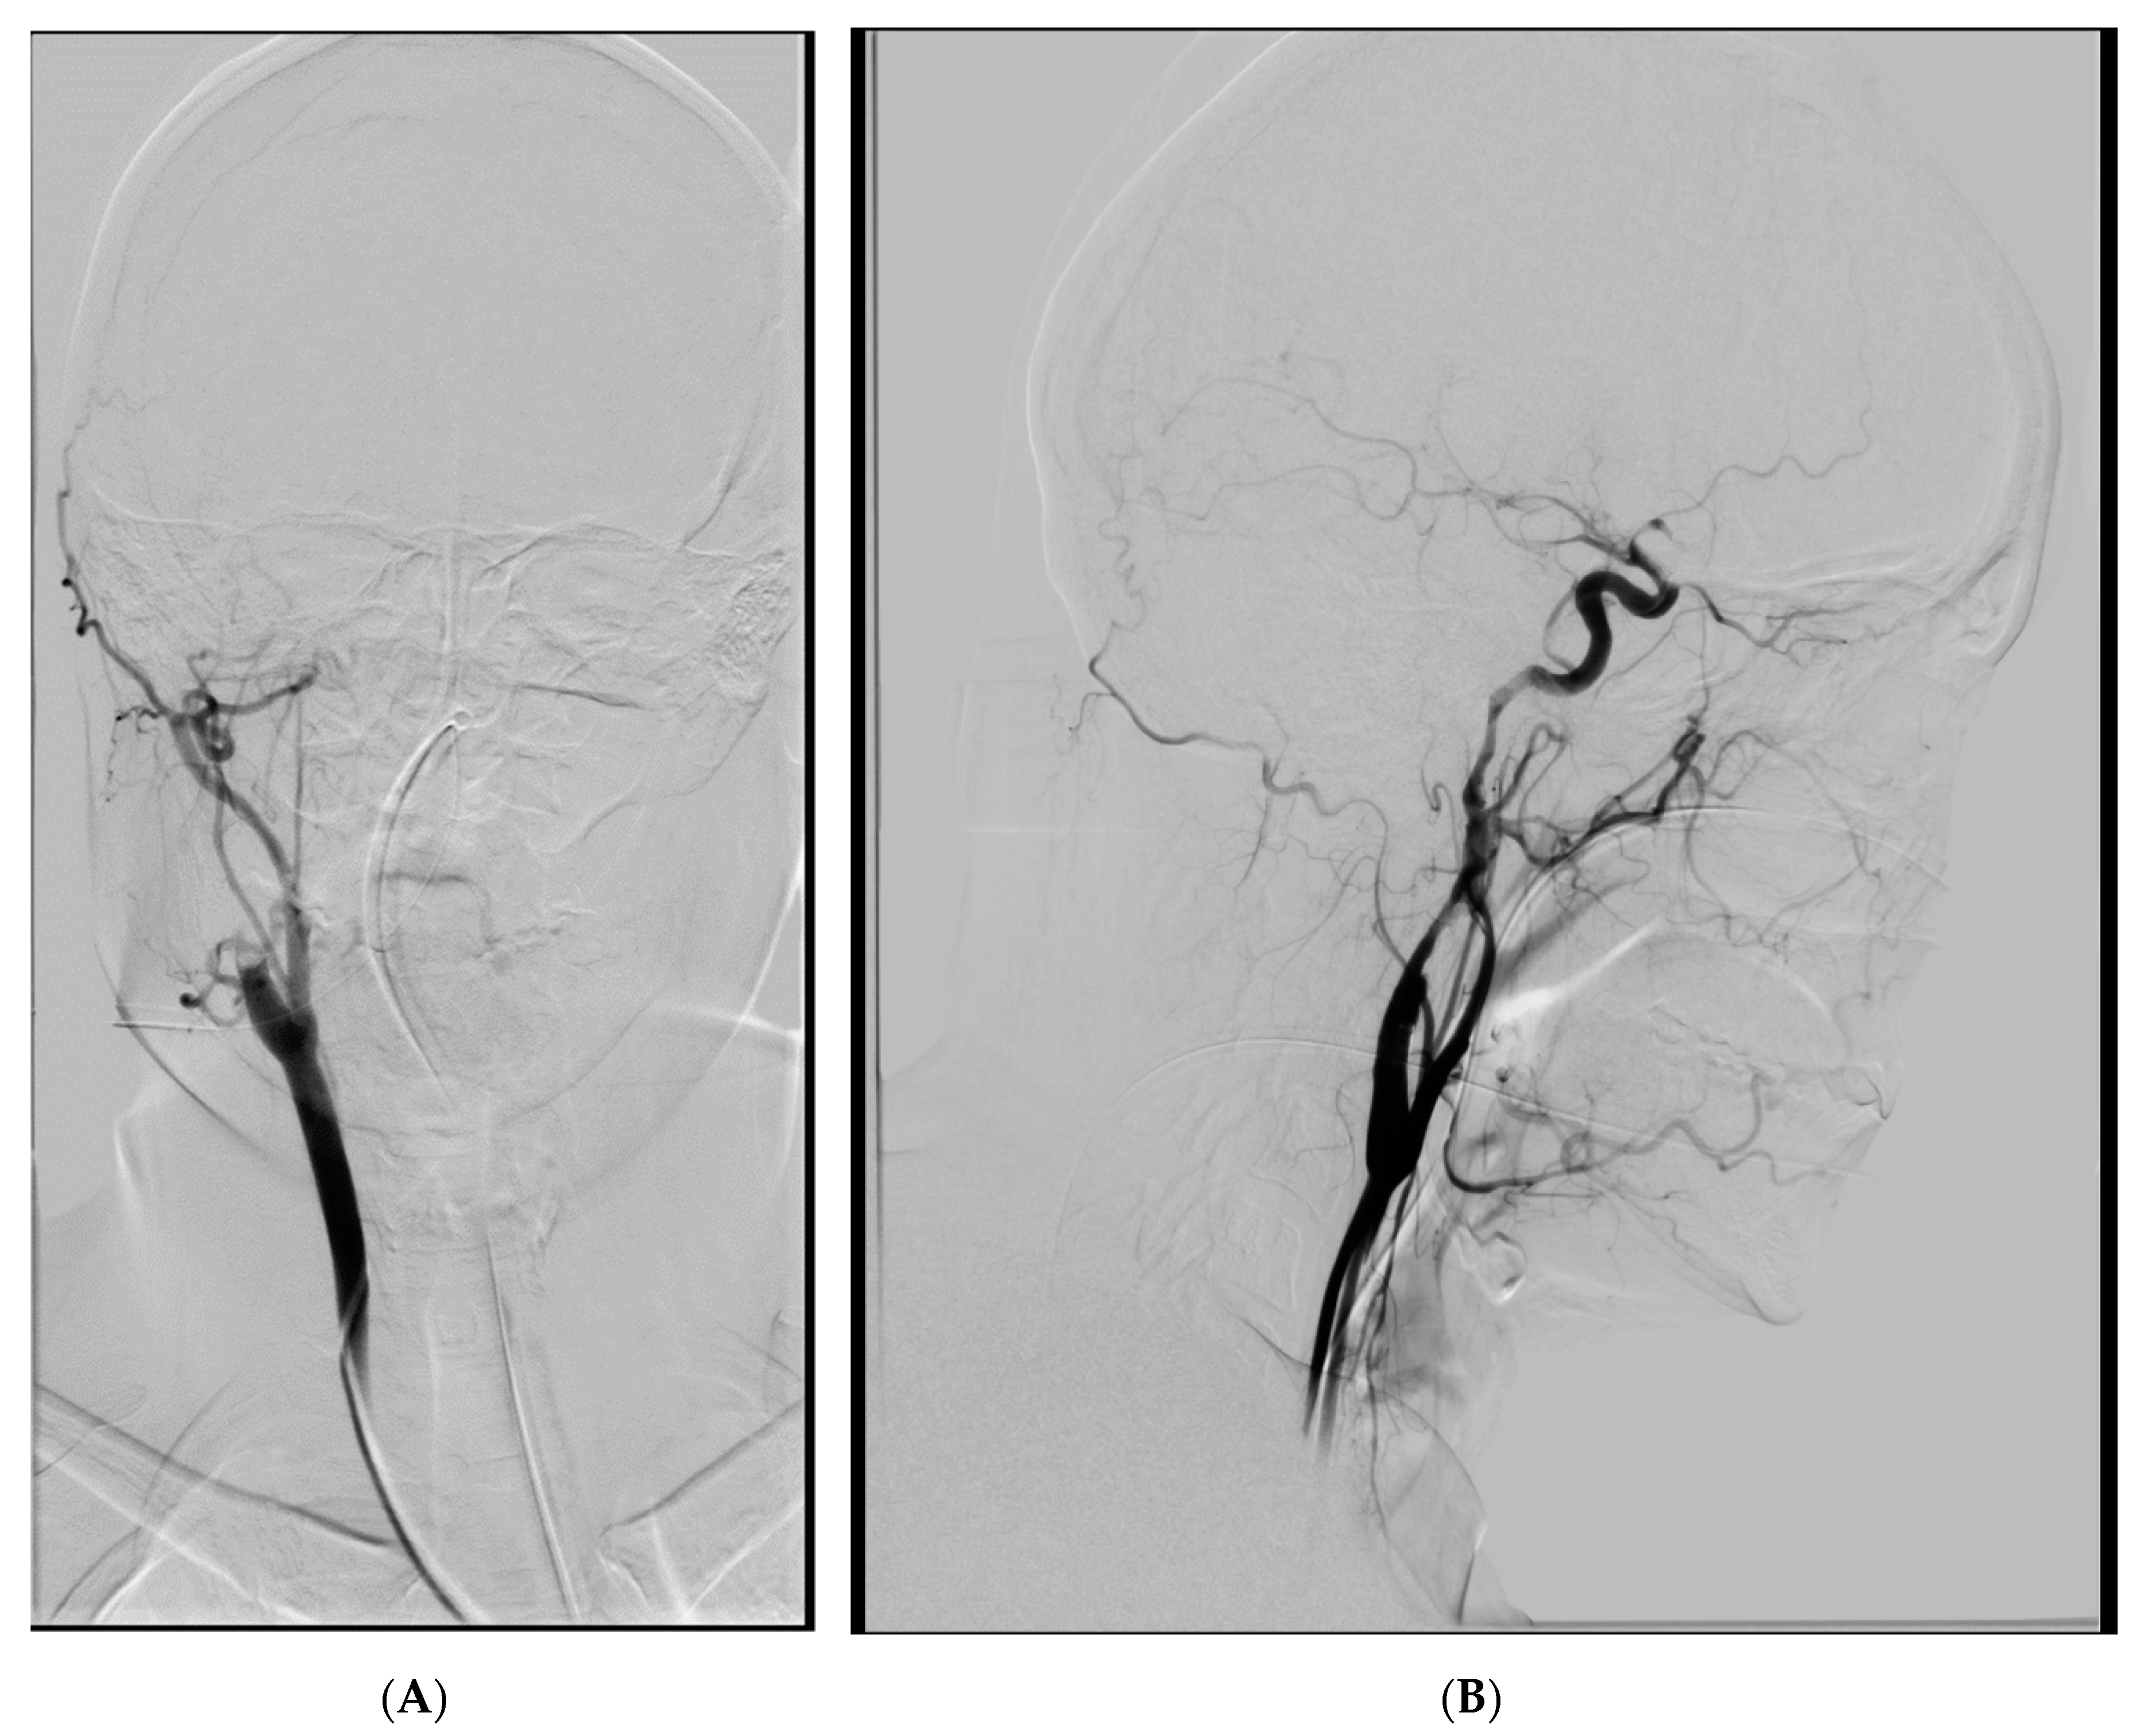

2. Case Presentation